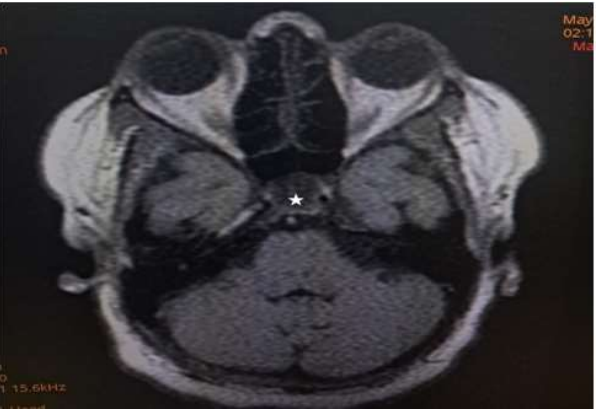

Magnetic Resonance Imaging (MRI) revealed expansion of the sella with a well-defined fairly rounded lesion measuring 15 X 14 X 15mm (width X AP X H). It is hypointense on T1W, hyperintense on T2W and suppressed on FLAIR sequence. Rim enhancement is seen post contrast. The mass is inseparable from the optic chiasma suggestive of compression.

Figure 1: Axial T1W image of the brain showing a hypointense rounded intrasellar mass lesion (white asterisk).

Rathke’s cyst is visualised on magnetic resonance imaging as a lesion located in the intermediate lobe of the pituitary. Its largest diameter usually does not exceed 20 mm9. The cyst may have varying intensity against the cerebrospinal fluid, although it is more often hypointense in T1-weighted images and hyperintense in T2-weighted images. RCC image captured on MRI is described as “an egg in a shell [9]. The enhancement of the cyst wall following contrast administration suggests inflammation or metaplasia [11].

Due to its high soft tissue resolution, Magnetic Resonance Imaging (MRI) is the primary diagnostic technique for RCC9. It also determines the cystic content and fluidity of the cyst which is useful in planning for subsequent patient’s management10. Fifty percent are hyperintense on T1W (due to high protein content) while 50% are hypointense. On T2W, 70% are hyperintense, 30% iso or hypointense and 20% have hypointense rim. T1W Post contrast images usually show no enhancement. However, a thin enhancing rim may be seen when cyst wall infection is present [19-20]. The case presented revealed expansion of the sella with a well-defined fairly rounded lesion measuring 15 X 14 X 15mm (width X AP X H). It is hypointense on T1W, hyperintense on T2W and suppressed on FLAIR sequence. Rim enhancement is seen post contrast. The mass is inseparable from the optic chiasma suggestive of compression. The appearance of the cyst confirmed no haemorrhage or debris within the cyst. However, the rim enhancement suggest inflammation of the cyst as explained in the text. The finding of optic chiasma compression may explain the visual impairment and the bitemporal hemianopia seen in the patient.